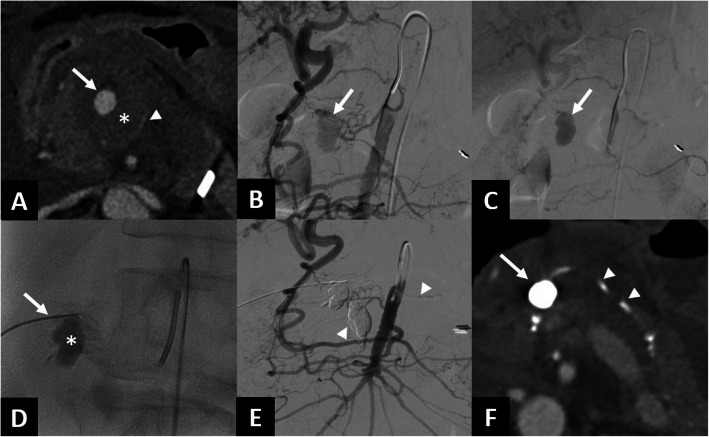

Background: The aim of this single-center retrospective study is to evaluate the feasibility, complications, and outcomes of transarterial embolization (TAE) for ruptured pancreaticoduodenal arcades aneurysms (PDAAs) due to median arcuate ligament (MAL), without subsequent revascularization of celiac artery (CA) occlusion/stenosis.

Methods: Between January 1st 2012 and June 1st 2024, all records from adult patients (≥ 18 years old) referred to our hospital for TAE due to ruptured PDAAs were retrospectively reviewed. All referrals were based on emergency clinical decisions and computed tomography. Procedure data included procedure, type of embolic agent and per-procedural complication. TAE technical success was defined as the cessation of aneurysm opacification immediately after the TAE, based on angiographic findings. Overall technical success was defined as the cessation of aneurysm opacification after TAE or percutaneous salvage approach during the same session. Then, we analyzed all published original articles published between January 2007 and December 2024 on emergency TAE of ruptured PDAAs due to MAL, without subsequent treatment of CA stenosis/occlusion.

Results: Nine patients (4 males) were referred for TAE for ruptured PDAAs due to MAL in our center. TAE technical success was achieved in 7/9 patients, and overall technical success was achieved in all patients. There were no major complications. No patients had rebleeding during follow-up. We reviewed four retrospective studies including 29 patients treated for ruptured PDAAs due to MAL without subsequent treatment of CA stenosis/occlusion. No patient received additional treatment for CA stenosis/occlusion. No aneurysm recurrence was diagnosed during the reported follow-up periods ranging from 1 to 65 months.

Conclusion: TAE for ruptured PDAAs without CA revascularization is safe and should be considered, although further studies are required to validate its validity and long-term outcomes.